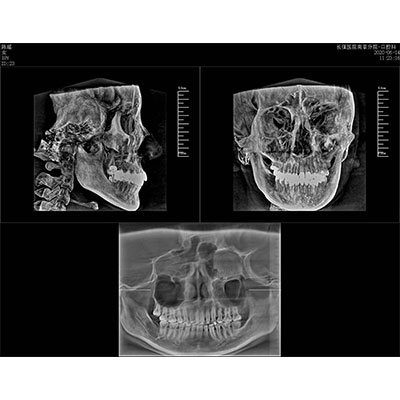

可同時(shí)觀察軸向面、冠狀面和矢狀面圖像,方便臨床診斷。